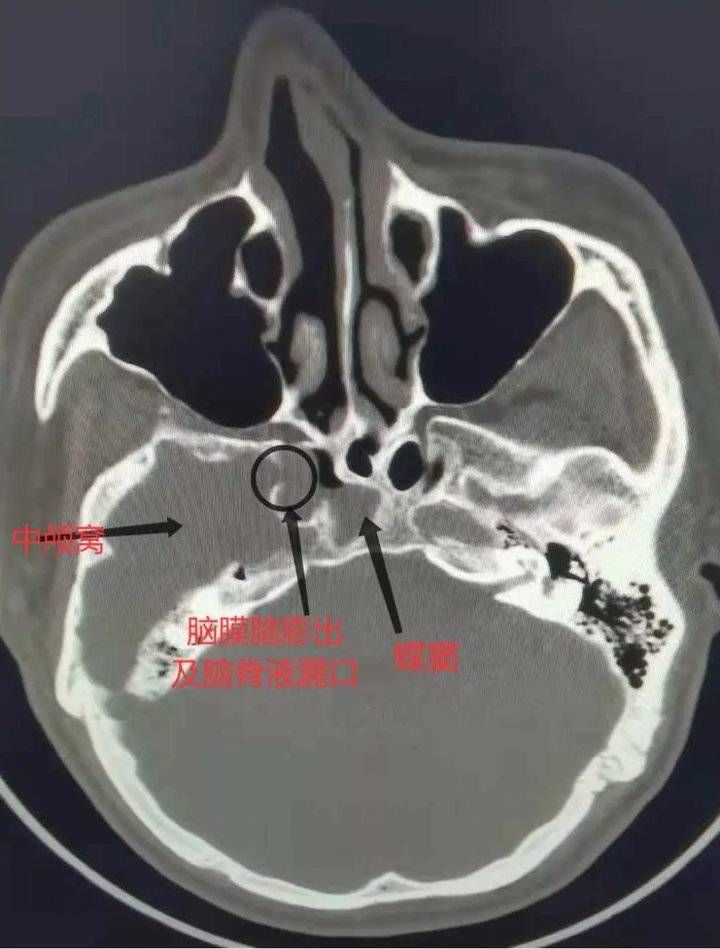

到院后,耳鼻咽喉-头颈外科主任赵秋良主任根据患者症状及查体,怀疑有脑脊液鼻漏可能,建议王先生做鼻窦CT检查。检查结果显示,患者右侧蝶窦外侧壁中颅窝处骨质缺损,右侧蝶窦积液,后完善脑脊液葡萄糖定量分析,确诊为自发性脑脊液鼻漏。为进一步手术治疗,立即为王先生办理了入院。